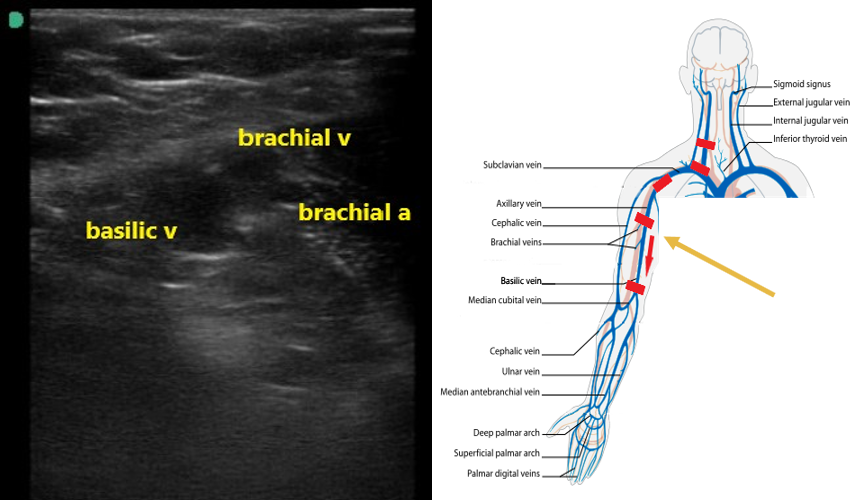

- The axillary vein going distally will split in the proximal humeral region into the basilic and 2 brachial veins (Fig. 7). The brachial veins will be paired with the brachial artery. The basilic vein is larger, more superficial, and runs medially between the biceps and triceps (Video 3).

- Figure 7. Basilic and brachial veins as well as the brachial artery in the proximal upper arm.

Video 3. Axillary vein scanning distally to split into basilic and 2 brachial veins. - Follow these veins to the antecubital fossa, compressing along their course.